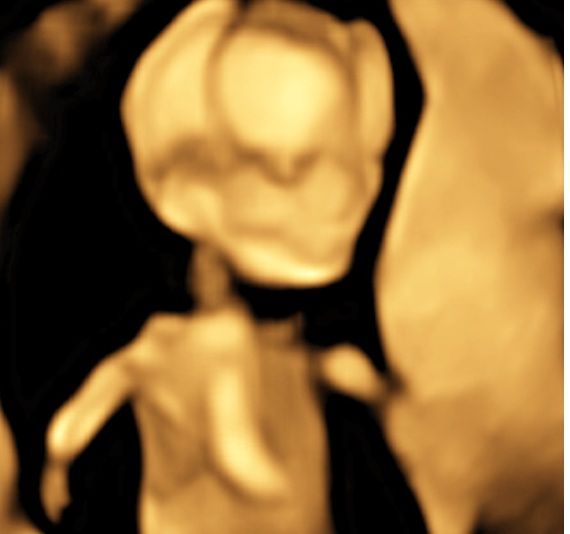

Realizamos las ecografías de viabilidad del embarazo, genética, morfológica, de bienestar fetal, ecocardiografías fetales, así como procedimientos invasivos como biopsia de vellosidades coriales y amniocentesis.